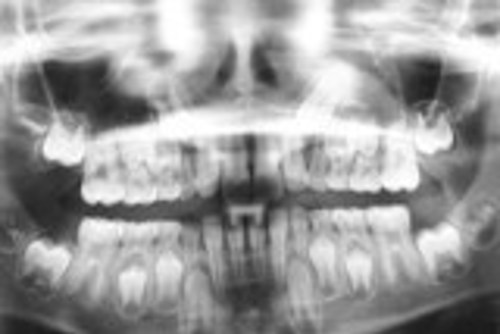

Tandskiftet begynder, når børnene når 6-årsalderen. Mælketænderne falder ud, og de blivende tænder kommer frem. Samtidig bryder 6-årstanden frem bagved de bageste mælketænder. Det er den første store blivende kindtand. Man taber ikke nogen mælketænder, dér hvor 6-årstanden kommer.

Det andet viser 6-årstanden der dukker op bagved den bagerste mælketand.

På dette røntgenbillede kan man se de nye tænder, som ligger i kæben neden under mælketænderne.